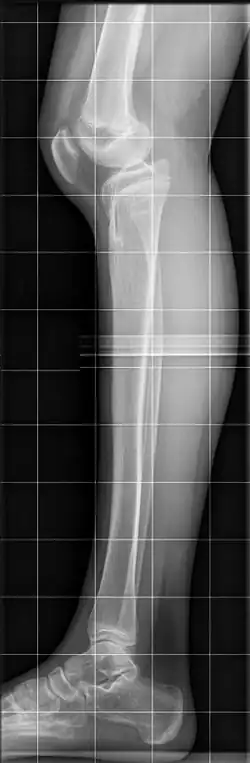

Das Genu recurvatum ist ein abnorm überstreckbares Knie. Während gesunde Erwachsene das Knie normalerweise in der Neutral-Null-Methode bis in 0-Stellung strecken können, gilt bei Kindern eine Überstreckbarkeit bis 10° als physiologisch, ab 15° als krankhaft.[2][3][4]

Die Fehlstellung kann bereits vorgeburtlich mittels Feinultraschall erkannt werden.[9] Die Diagnose ergibt sich bei der körperlichen Untersuchung, die Abklärung der Ursache erfolgt durch eine Röntgenaufnahme vorzugsweise belastet (im Stehen).[3][7] Normalerweise ist das Tibiaplateau nach dorsal (hinten) um 7–10° geneigt, beim Genu recurvatum ist diese Neigung vermindert, aufgehoben oder nach ventral abgeflacht.[8][2]